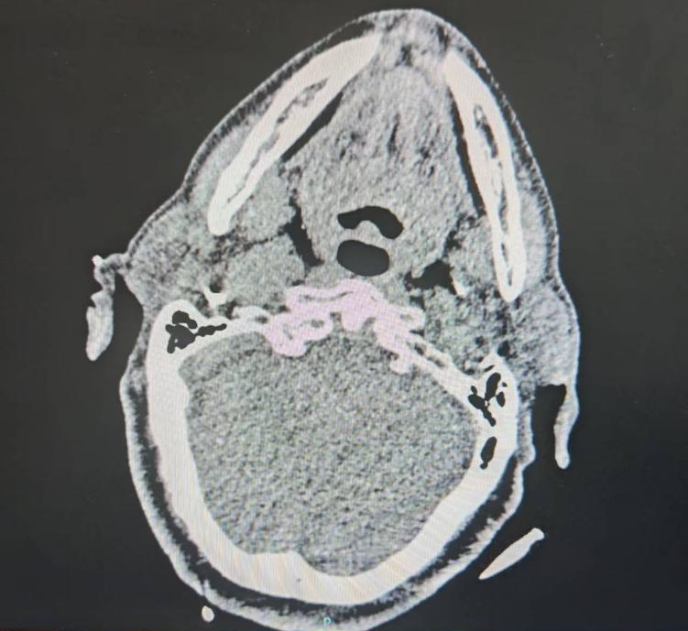

- 机器人辅助半月节电刺激治疗顽固性三叉神经痛1例 三叉神经痛是一种临床常见的面部神经痛,其特征是三叉神经分布的面部区域自发或诱发的电击样痛或刺痛,疼痛较剧烈。2018年头痛疾病国际分类第三版(ICHD-3)将三叉神经痛(TN)分为经典性三叉神经痛、继发性三叉神经痛和特发性三叉神经痛。……